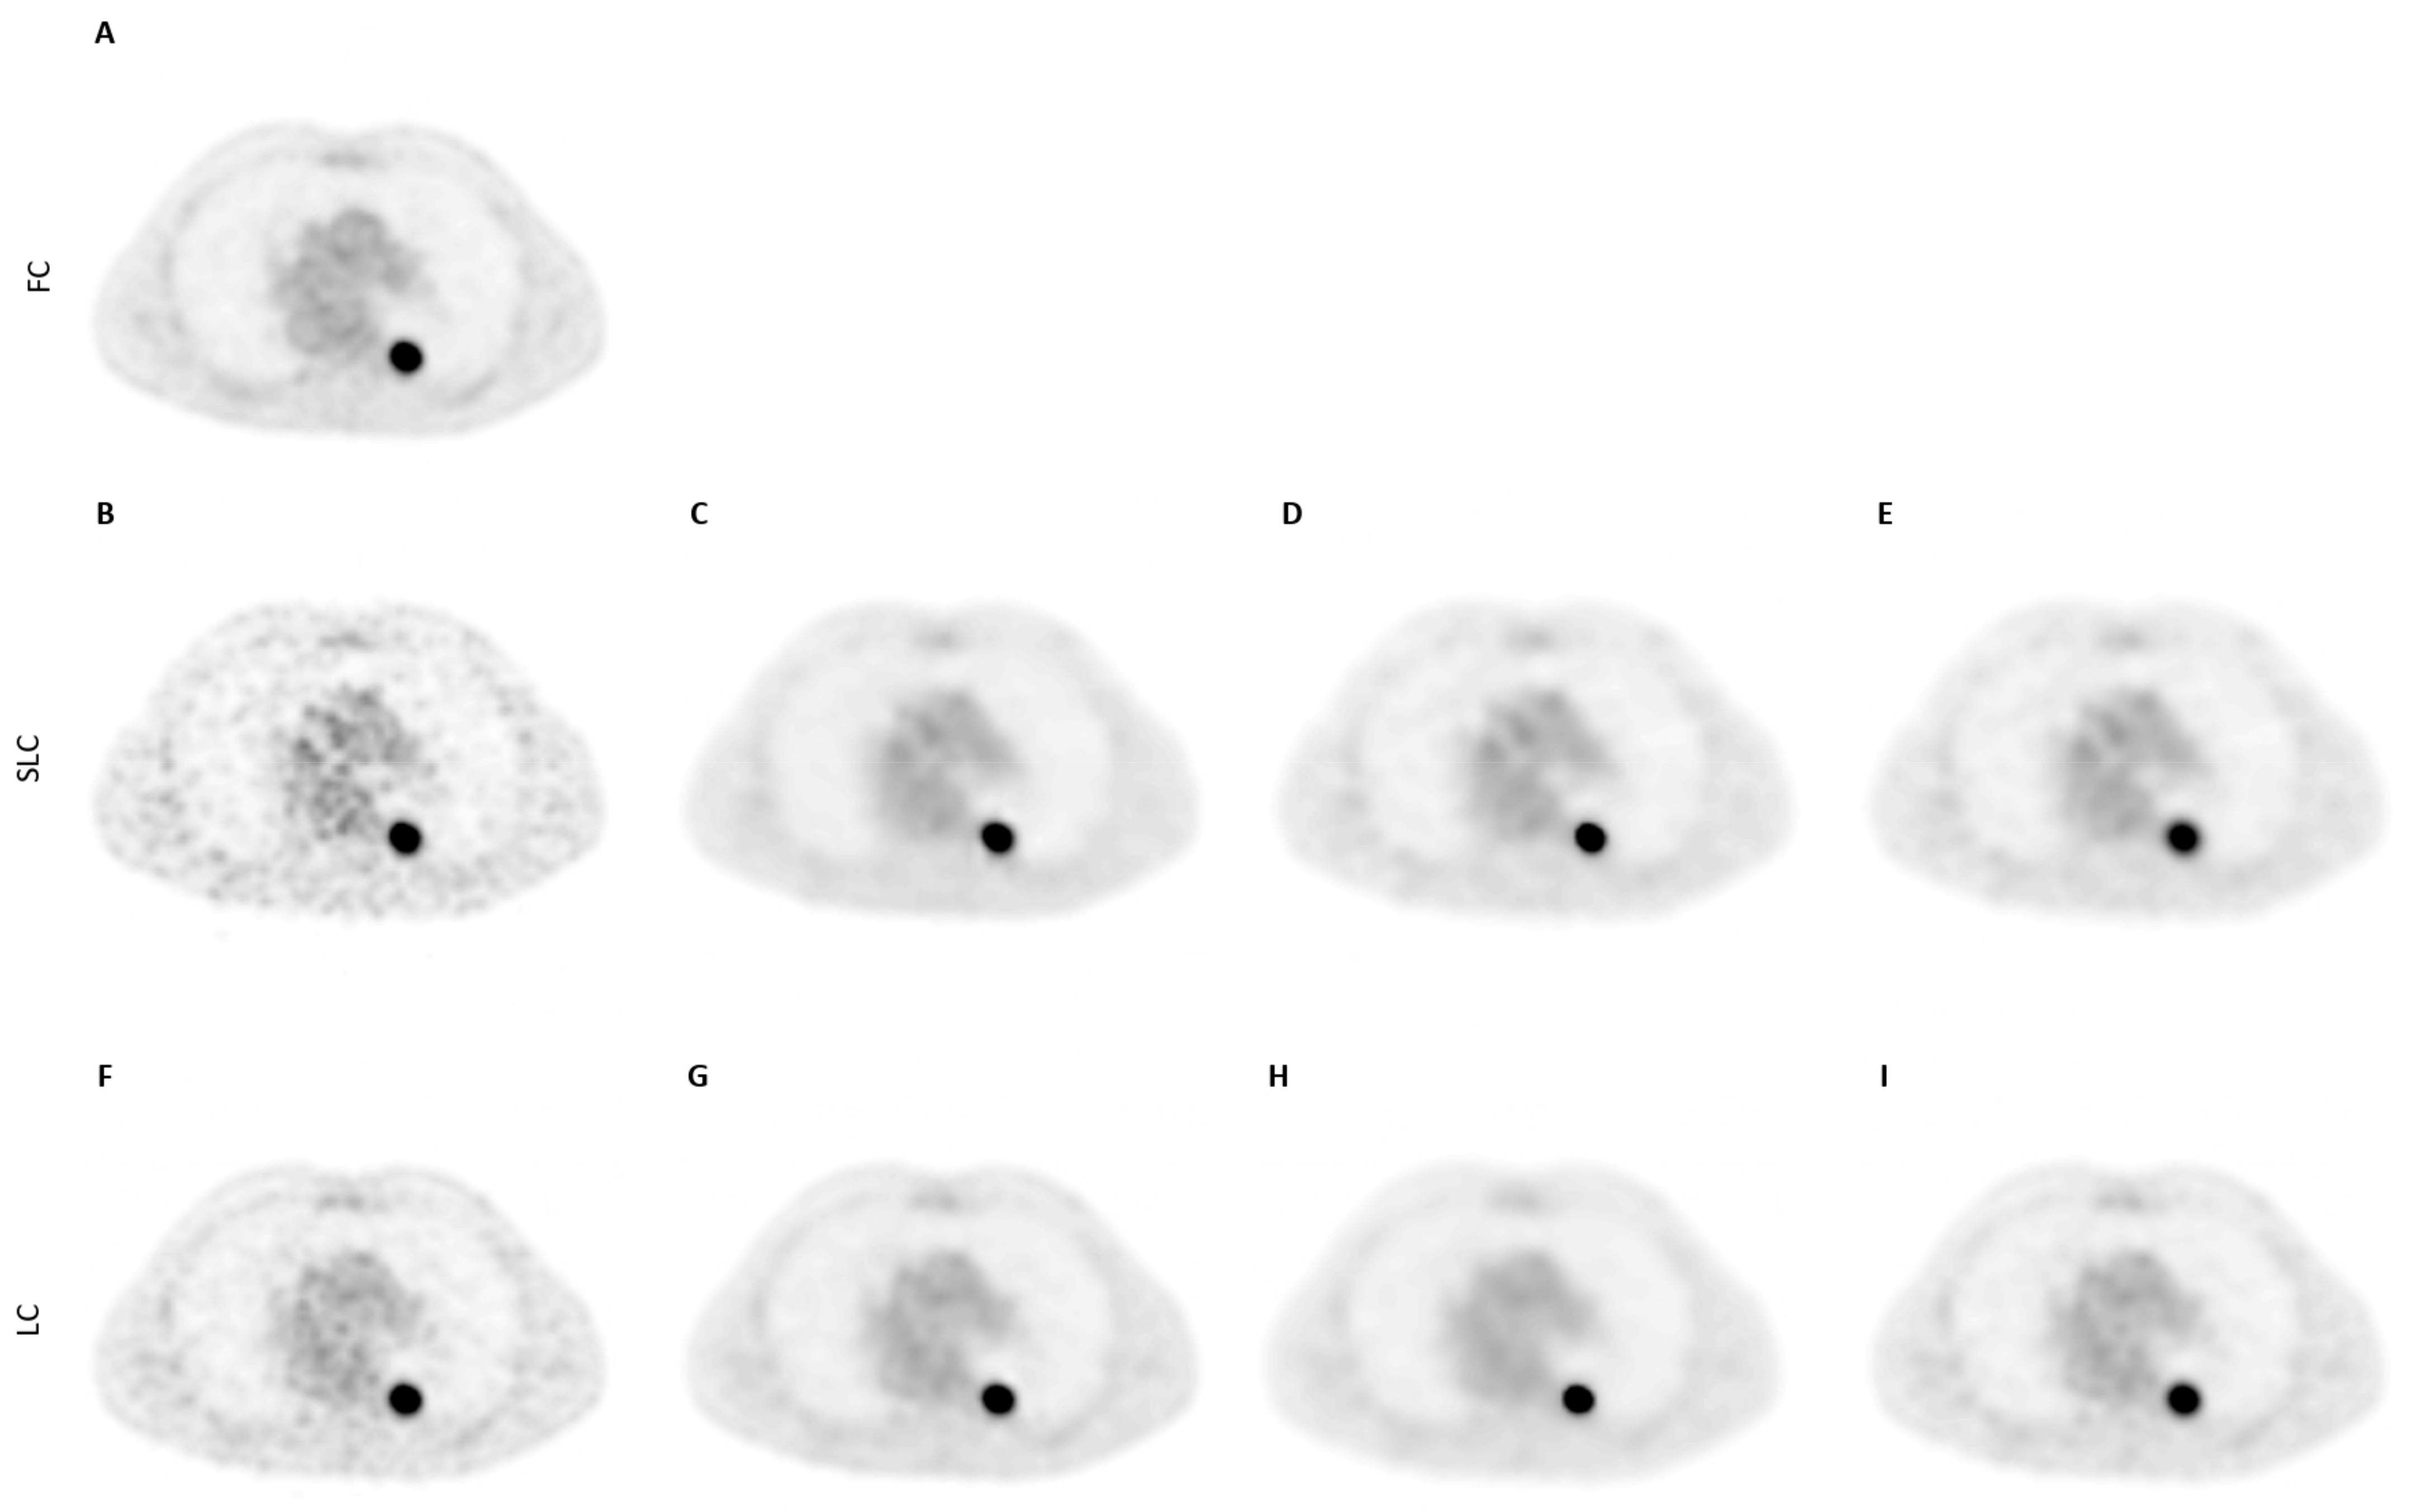

| SLC | LC | FC | |||||

|---|---|---|---|---|---|---|---|

| Metrics [1–5: Low–High] | SLC-CNN | BF-4 mm | BF-5 mm | LC-CNN | BF-3 mm | BF-4 mm | |

| Level of noise | 3.0–3.2 | 4.0–4.0 * | 3.6–4.0 * | 1.8–2.0 | 2.6–2.0 ** | 2.2–3.8 * | 1–1 * |

| Tumour detectability | 2.0–3.0 | 2.2–3.0 | 2.0–3.0 | 4.0–4.0 | 3.6–4.0 | 2.8–3.0 * | 5–5 * |

| Overall scan quality | 2.4–2.6 | 1.6–2.0 * | 1.8–2.0 * | 4.4–4.0 | 3.8–4.0 | 2.8–2.2 * | 5–5 * |

| Clinically acceptable? [%] | 0–80 | 0–0 * | 0–0 * | 100–100 | 80–100 | 20–0 * | 100–100 |

| Best scan (1/2/3/4) | 2–2 | 3–3 | 4–4 | 2–3 | 3–2 | 4–4 | 1–1 |